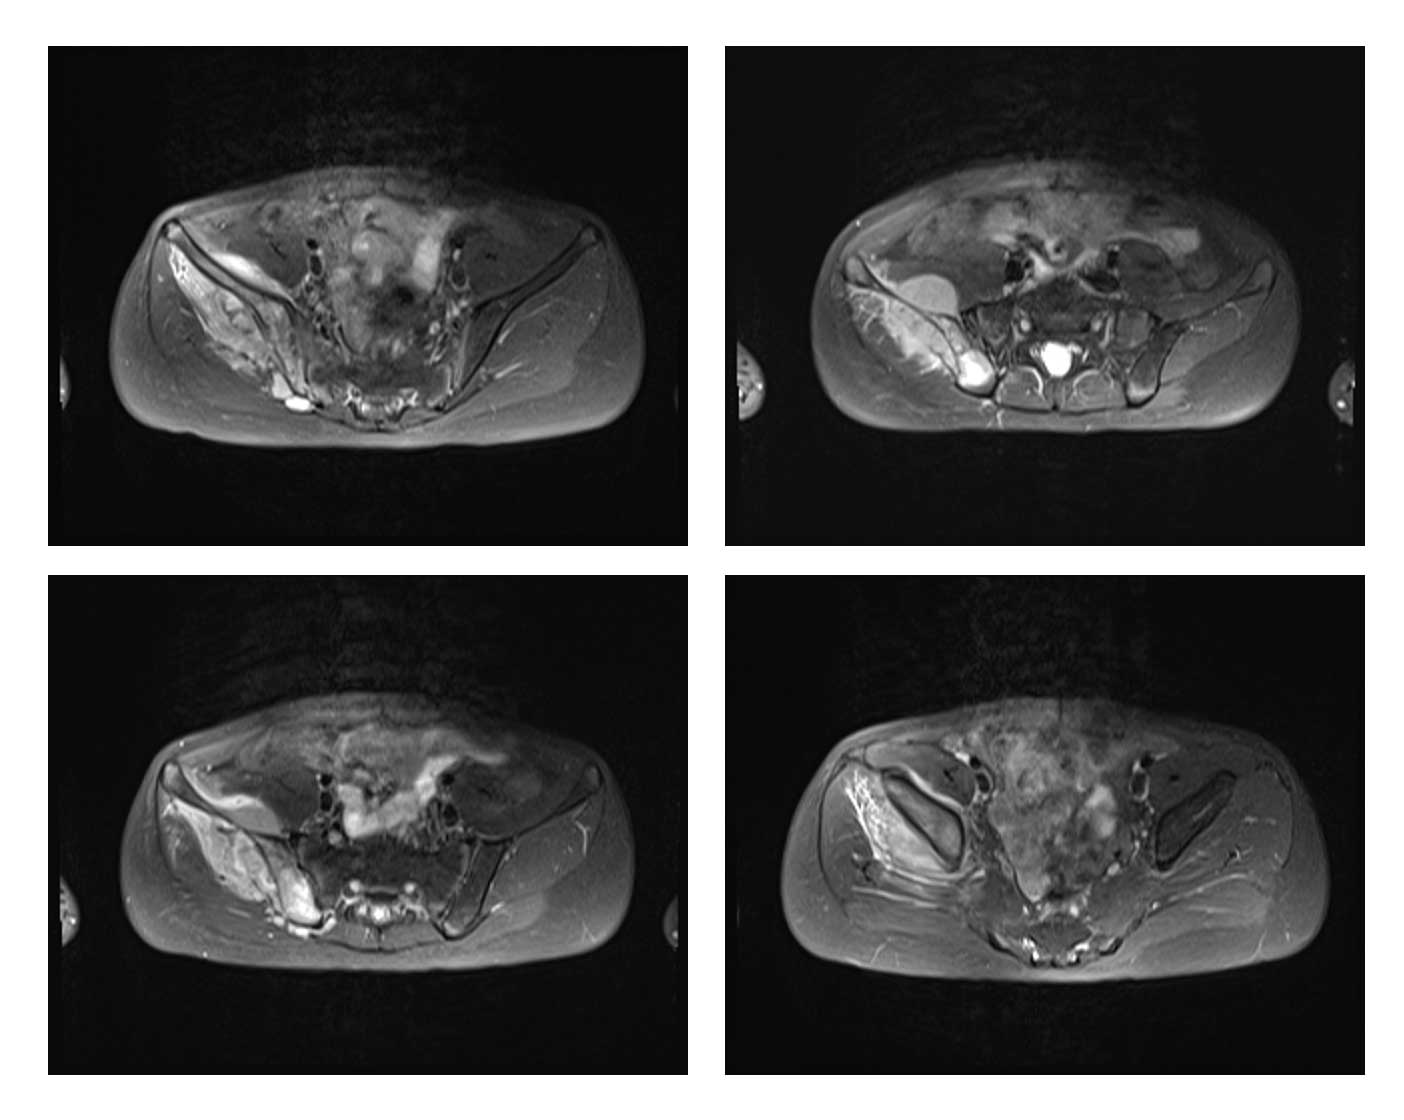

Ameliyat Öncesi: MR’da sağ ilaika kanatta yumuşak doku kitlesinin eşlik ettiği tümör dokusu görülmekte.

Radyolojik tetkiklerde sağ iliak kanat yerleşimli kemik harabiyetine yol açan kitle saptandı.